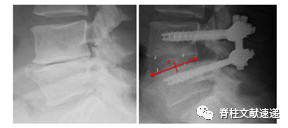

该文献选取了83位接受单节段PLIF术的患者,对其进行随访观察,根据其影像学资料,记录cage大小及位置。通过比较中心点比率(CPR)、后间隙比率(PGR)(CPR和PGR计算方法见下图)和术前术后腰椎前凸度数的变化(测量方法见下图)之间的关系,来评估PLIF术中cage的大小和放置的位置对术后恢复腰椎生理性前凸有何影响。

图注:单节段腰椎前凸的测量。

图注:所有cage内部均有标记cage位置的金属标志,通过该标志可以确定cage的中心点。然后计算出CPR和PGR,左图为中心点比率(CPR)计算方法:cage中点至下椎体后边缘的长度(X)除以下椎体上终板的长度(Y),CPR值小于0.5表示笼子放置在椎间盘间隙的后部,而值大于0.5表示笼子放置在椎间盘的前部。右图为后间隙比(PGR)计算方法:cage后壁至下椎体后边缘的长度(X)除以下椎体上终板的长度(Y),该比率不仅表明笼子位置(比率越大,笼子越靠前),也间接表明笼子的长度。

图注:根据该文献cage定位标准,该患者cage为相对靠前放置

图注:根据该文献cage定位标准,该患者cage为相对靠后放置